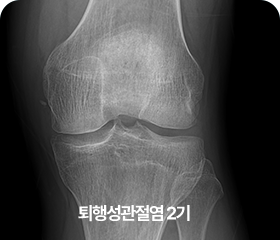

단계별 퇴행성 관절염 증상

2기